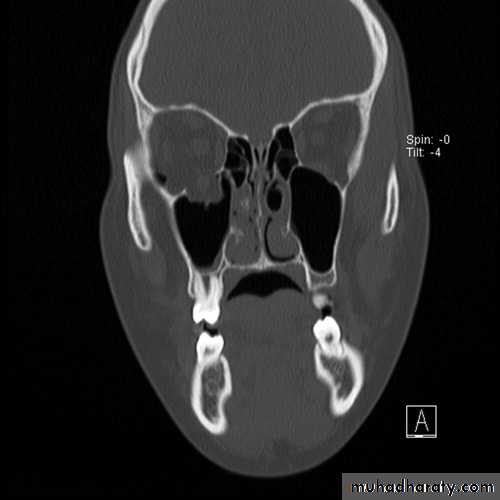

RADIOGRAPHIC EXAMINATION

Computed TomographyCT is the gold standard for radiographic evaluation of zygomatic fractures. Axial and coronal images are obtained to define fracture patterns, degree of displacement, and comminution and to evaluate the orbital soft tissues.